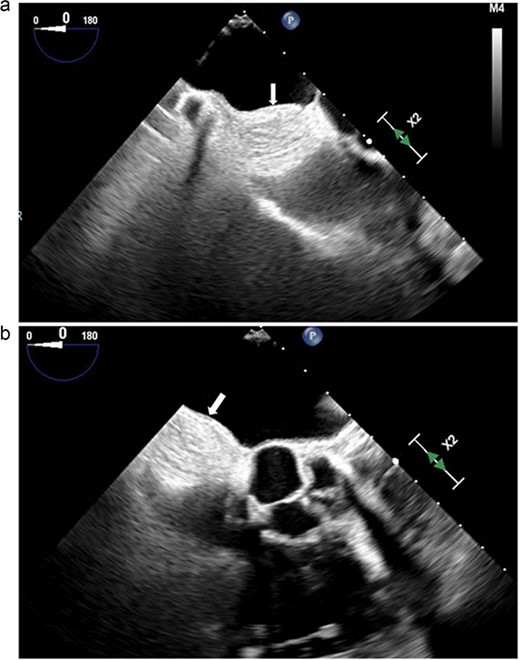

Electrocardiography revealed normal sinus rhythm. An echocardiogram was performed, which revealed a mass involving the interatrial septum extending superiorly toward the superior vena cava (Fig. 1). She had normal biventricular function with a left ventricular ejection fraction of 55%, no valvular abnormalities, and no evidence of obstruction. Subsequently, cardiac magnetic resonance imaging (MRI) was performed. This showed a 5.5 cm x 2.5 cm x 2.5 cm mass involving the interatrial septum with near encasement of the superior vena cava (Fig. 1). The mass extended inferiorly toward the inferior vena cava (IVC) and coronary sinus, but without obvious involvement. The mass was hyperintense on T1 and T2-weighted sequences. On T1 fat saturating images, it was hypointense. It showed contrast enhancement with gadolinium suggesting vascularity. The staging workup further included positron emission tomography (PET), which showed increased fluorodeoxyglucose-18 (FDG) uptake in the atrial tumor without evidence of extracardiac disease or metastases (Fig. 2b). These findings were suggestive of a primary cardiac liposarcoma. The patient was then referred to our clinic for consideration of resection. She was deemed an operable candidate and the tumor resectable.

(a and b) Transesophageal echocardiogram. Arrow denotes mass involving the interatrial septum.